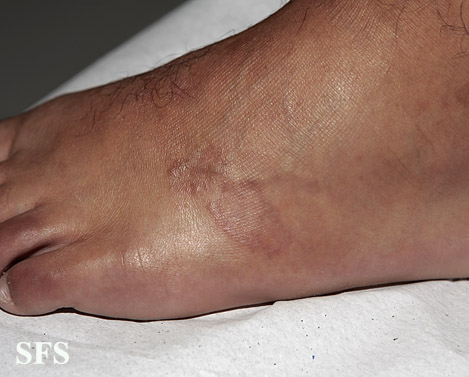

granuloma annulare